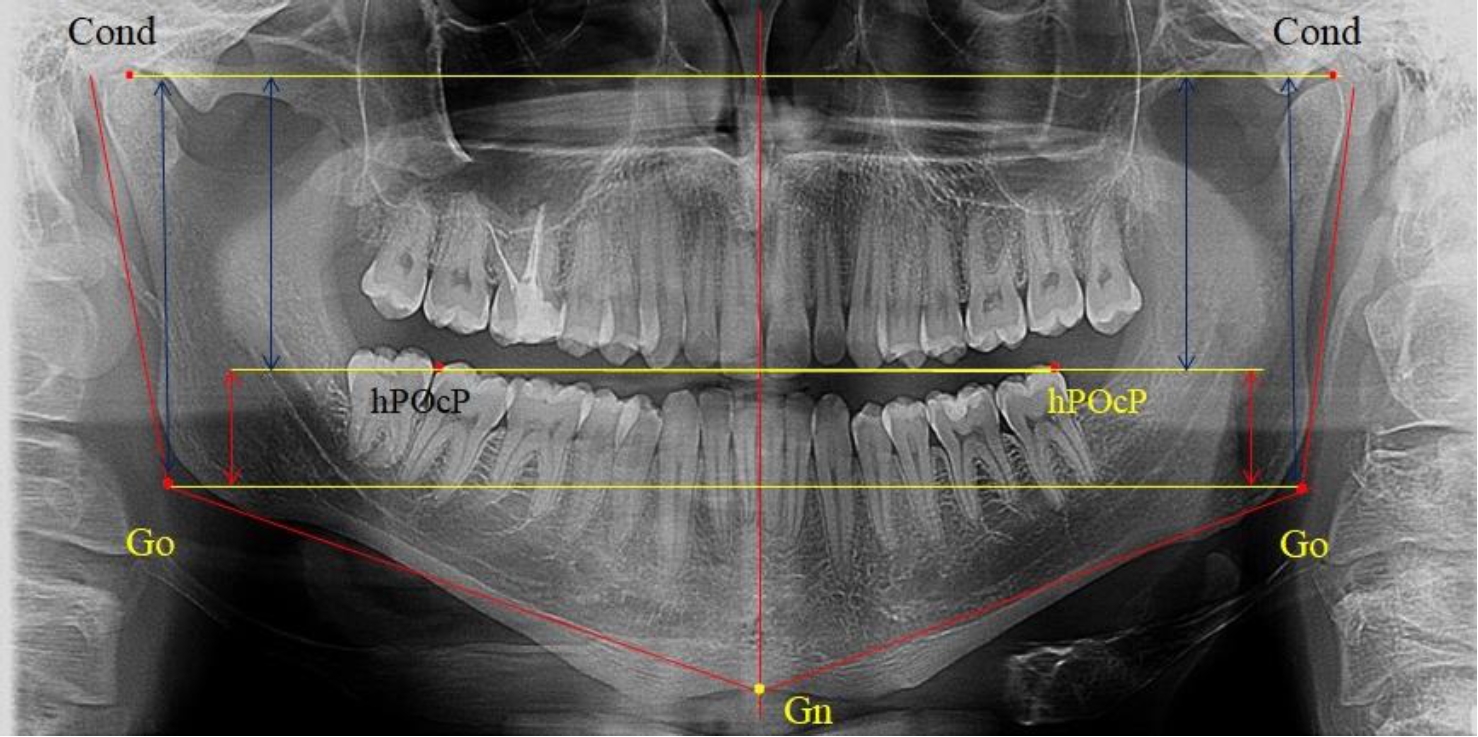

На боковых телерентгенограммах определяли положение верхней точки суставной головки Cond. Касательные линии к ветви и телу нижней челюсти пересекались в точке, которую в клинической практике обозначают как точка угла нижней челюсти или точка гонион Go. Точкой hPOcP обозначали дистальный бугорок нижнего второго моляра вблизи окклюзионного контура коронки, через нее от межрезцовой точки проводили окклюзионную линию, ее продолжали до задней части ветви челюсти. Высоту ветви измеряли как расстояние от угла нижней челюсти до вершины суставной головки Go-Cond. Общую высоту ветви условно делили на 2 части, ее границей служила окклюзионная линия. Верхнюю часть обозначали как окклюзионно-суставная, а нижнюю – как окклюзионно-гониональная.

На ортопантомограмме использовали аналогичные суставные точки Cond на каждой стороне, их соединяли между собой суставной линией Cond-Cond.

Касательная к ветви нижней челюсти соединяла выступающие точку. При построении касательной к телу челюсти проводили в обе стороны линии от точки Gn, расположенной в нижней центральной части подбородочного симфиза, до выступающей нижней точки угла челюсти. Касательные линии при пересечении определяли конструктивную точку гонион Go. Соединение гониональных точек определяло положение гониональной линии Go-Go. При соединении окклюзионных точек hPOcP получали окклюзионную горизонталь (рис. 1). Измеряли расстояние между горизонталями в области ветвей нижней челюсти. Статистический анализ проводили в программе Microsoft Excel. Составляли вариационные ряды с последующим расчетом среднего значения, стандартного отклонения и ошибки среднего ±m. Также оценивали максимальные и минимальные значения величин. Определи относительные величины соотношения верхней и нижней частей ветви нижней челюсти.

Рис. 1. Метод измерения высоты ветви нижней челюсти на телерентгенограмме (а) и ортопантомограмме (б)

В 1-ю подгруппу были включены 36 комплектов телерентгенограмм и ортопантомограмм [или (48,65 ± 5,81) % от общего количества], на которых средняя величина отношения верхней части ветви к нижней составляла 1,95 ± 0,03, что соответствовало показателям, полученным по группе в среднем, но с меньшим показателем ошибки среднего значения. Визуально верхняя окклюзионно-суставная часть выглядела вдвое больше нижней окклюзионно-гониональной (рис. 2). При этом высота ветви составляла (62,09 ± 1,22) мм. Максимальная высота была 71 мм, а минимальная – 55 мм. Высота верхней части составляла (41,02 ± 0,77) мм, а высота нижнего отдела ветви была (21,09 ± 0,51) мм.

Рис. 2. ОПТГ пациента 1-й группы с оптимальным коэффициентом соотношения частей ветви нижней челюсти